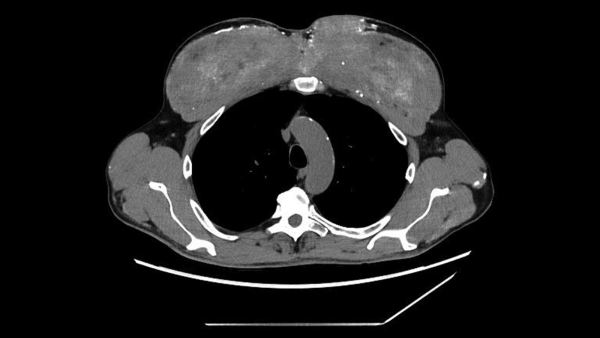

Комп'ютерна томографія грудної клітки чоловіка виявила кальцифіковані ділянки грудних м'язів, куди він раніше вводив олії для покращення м'язової маси. (Зображення надано: Markowska et al. BMC Nephrol 26, 476 (2025). (CC 4.0))

Чоловік загалом був стабільним, але медичний огляд показав помітні зміни в м’язах плеча та грудей, що відповідали порушенням, виявленим на сканах. Потім лікарі переглянули історію хвороби пацієнта, і він поділився важливою деталлю: приблизно 30 років тому він почав отримувати «невідомі внутрішньом’язові ін’єкції (ймовірно, що містять тестостерон)» у м’язи грудей та плечей для їх збільшення, згідно зі звітом про його випадок.

Діагноз: під мікроскопом м'яз був заповнений силіконополімерною речовиною на масляній основі та оточений щільними кальцієвими відкладеннями. Команда вчених дійшла висновку, що попередні ін'єкції чоловіка в м'язи, ймовірно, містили синтол, речовину, що складається переважно з олії, яка візуально «наповнює» м'язи, по суті, надуваючи їх, як водяні кульки.

У цьому випадку синтол викликав стійку реакцію на чужорідне тіло — організм, по суті, реагував на матеріал, який він не міг розщепити. З часом ця реакція призвела до рубцювання та кальцифікації, що призвело до накопичення великої кількості кальцію всередині м'яза. І зрештою цей кальцій потрапив у його кров.